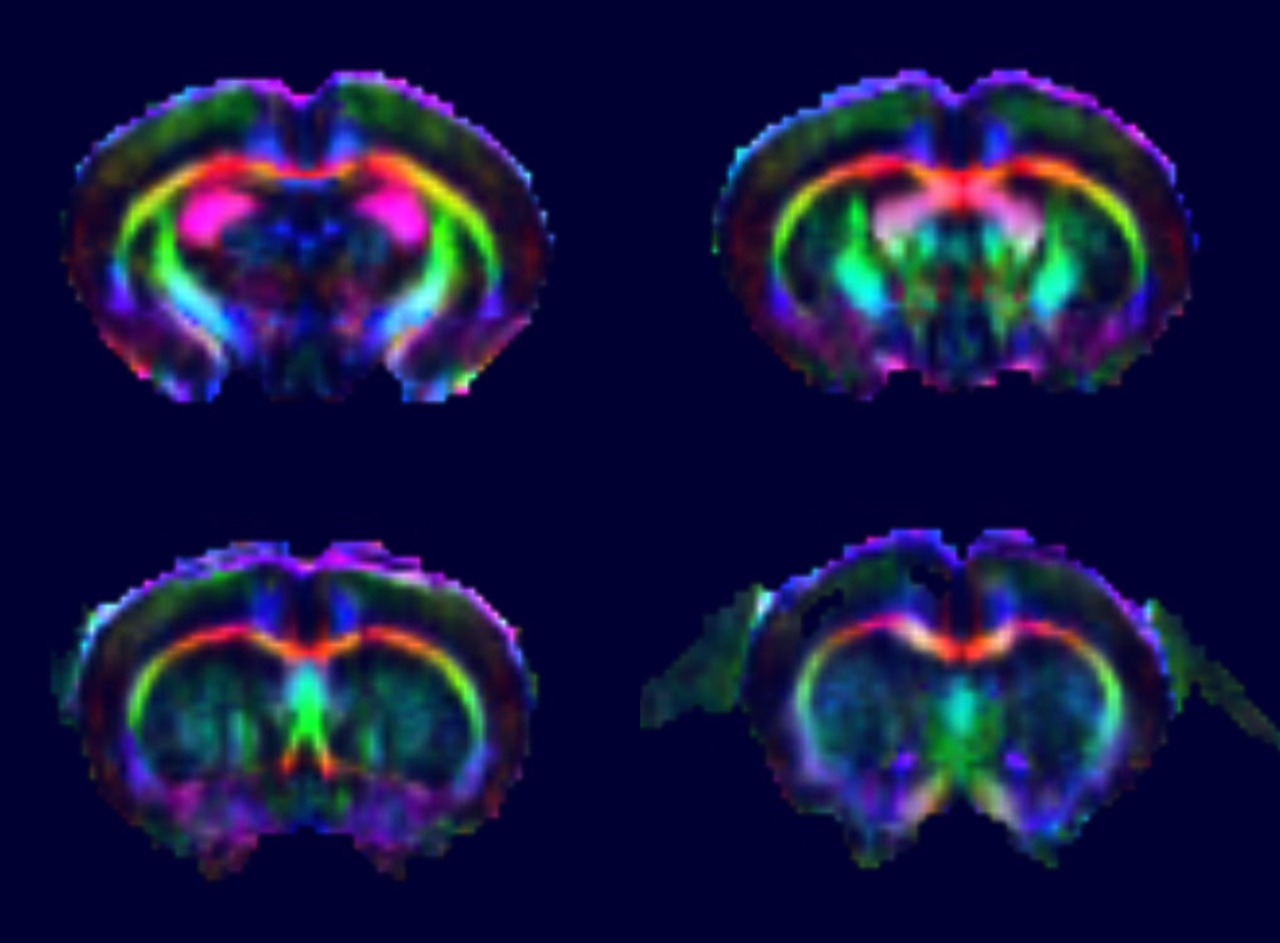

DTI at 9.4 T

Single-shot EPI DTI maps were acquired with 30 diffusion directions in only 1 min 45 s using the 1H receive-only 2 x 2 rat brain surface array coil